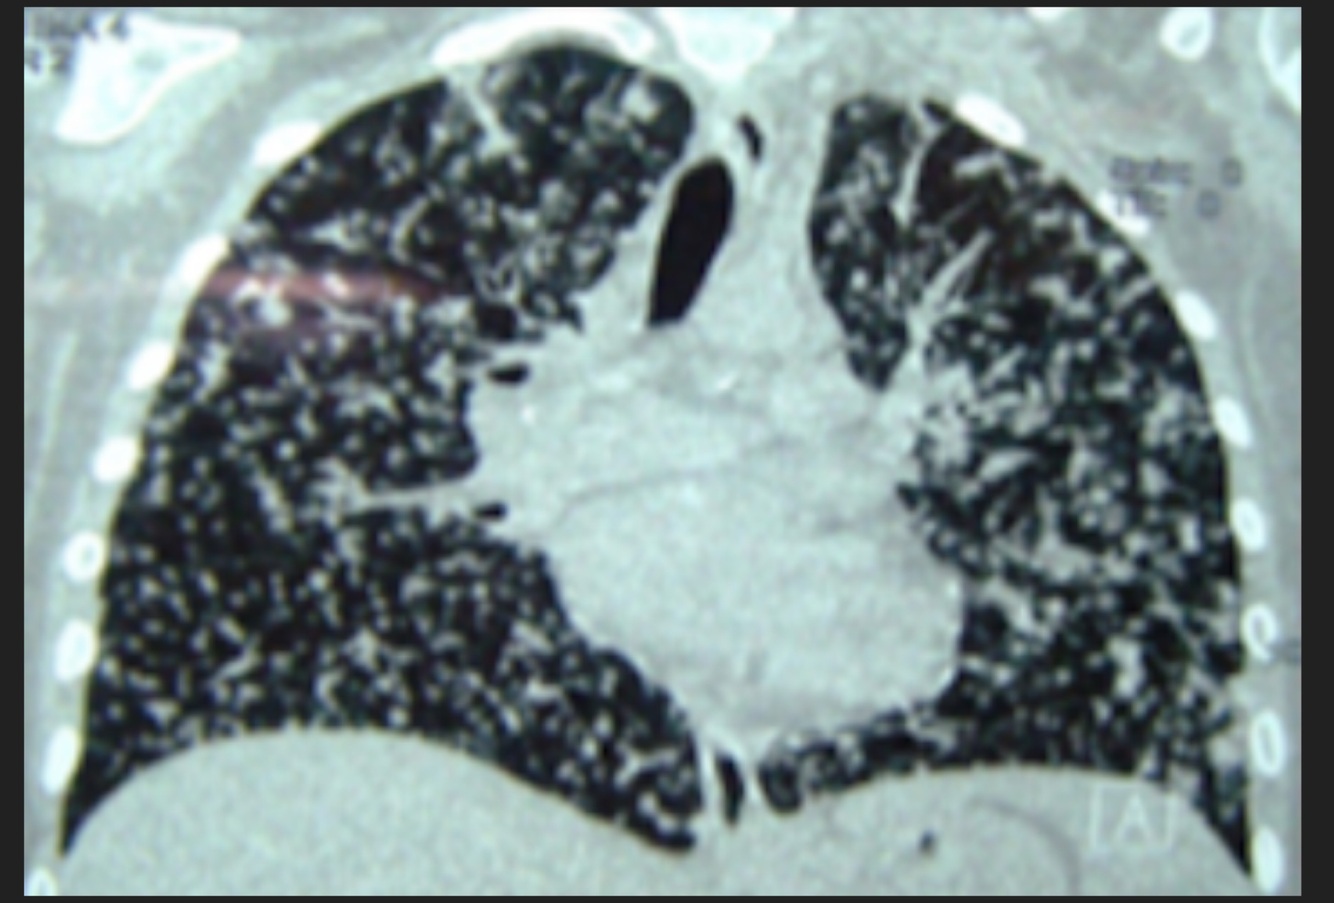

Q

Masculino de 66 años de edad, cuenta con el diagnóstico de VIH positivo, con fiebre, disnea

A

TB Miliar